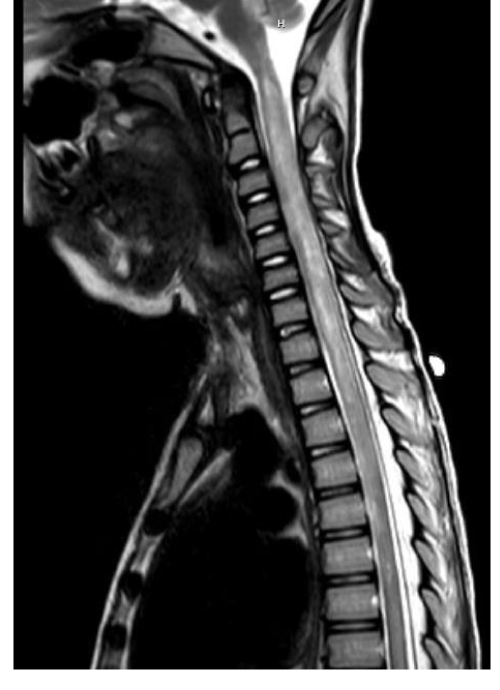

Quadraplegia: A Rare Complication Associated with Cricotracheal and Tracheal Resection

Jennifer F. Ha* and Glenn E. Green

Introduction: Cricotracheal resections and tracheal resections are highly successful procedures for the treatment of severe airway pathology including high-grade stenoses.